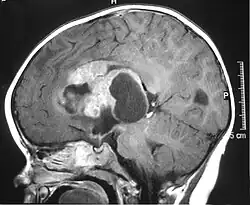

MRI of an AT/RT | |

The initial diagnosis of a tumor is made with a radiographic study (MRI[28] or CT-). If CT was performed first, an MRI is usually performed as the images are often more detailed and may reveal previously undetected metastatic tumors in other locations of the brain. In addition, an MRI of the spine is usually performed. The AT/RT tumor often spreads to the spine. AT/RT is difficult to diagnose only from radiographic study; usually, a pathologist must perform a cytological or genetic analysis.

Appearance on radiologic exam

AT/RTs can occur at any sites within the CNS; however, about 60% are located in the posterior fossa or cerebellar area. The ASCO study showed 52% posterior fossa; 39% sPNET; 5% pineal; 2% spinal, and 2% multifocal.[3]

The tumors' appearance on CT and MRI are not specific, tending towards large size, calcifications, necrosis (tissue death), and hemorrhage (bleeding). Radiological studies alone cannot identify AT/RT; a pathologist almost always has to evaluate a brain tissue sample.

The increased cellularity of the tumor may make the appearance on an uncontrasted CT to have increased attenuation. Solid parts of the tumor often enhance with contrast MRI finding on T1 and T2 weighted images are variable. Precontrast T2 weighted images may show an isosignal or slightly hypersignal. Solid components of the tumor may enhance with contrast, but not always. MRI studies appear to be more able to pick up metastatic foci in other intracranial locations, as well as intraspinal locations.